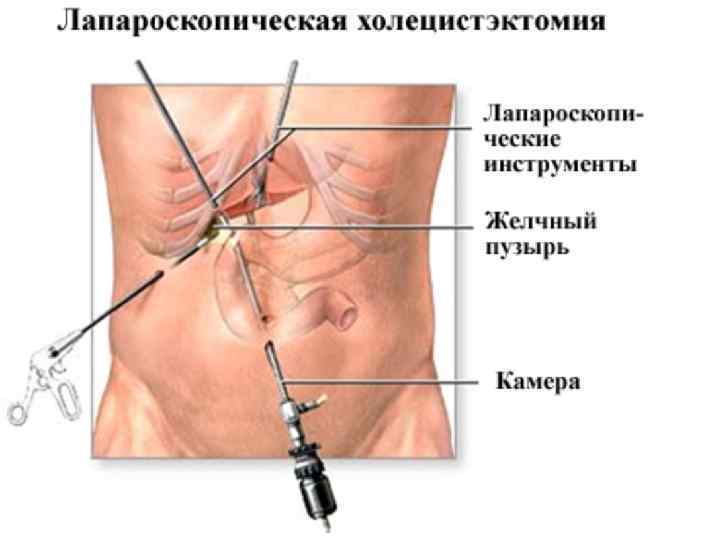

Лапароскопиялық холецистоэктомия Көрсеткіші: жедел холецистит (егер операцияны ауыру басталғаннан 48 сағат аралығында жасаса). Қарсы көрсеткіштері: айқын жүрек-өкпелік жеткіліксіздік; емге көнбейтін қан ұю бұзылыстары; жайылған перитонит; іштің алдыңғы қабырғасының қабыну өзгерістері; жүктілік (II-III триместр); семіздік III-IV степень; ауыру басталғаннан 48 сағаттан кейін; механикалық сарғаю; іш қуысының жоғарғы этажында бұрын болған операциялар кезінде.